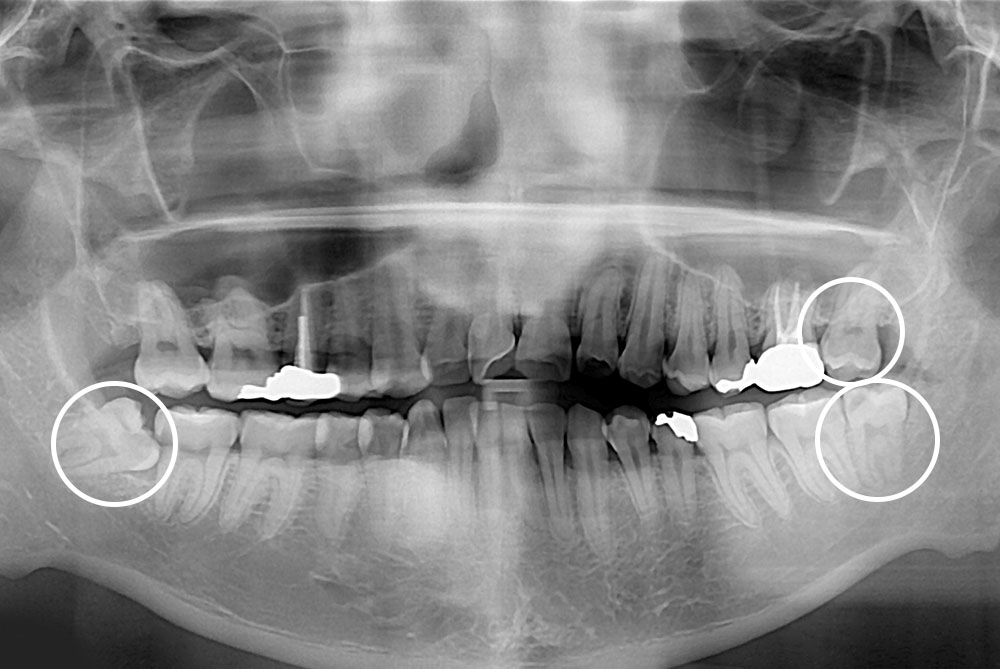

[사랑니] 매복 사랑니 발치

치료후 : 2020-06-30

세종치과는 구강악안면외과학 박사이신 원장님이 발치하는 치과입니다.